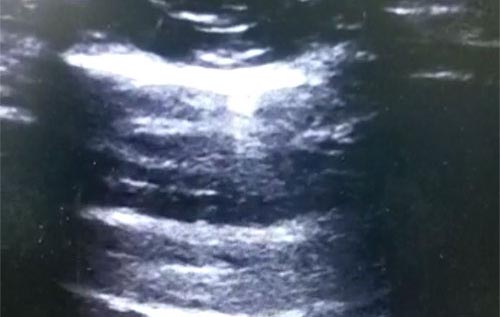

Semana 10

Qual o nome popular da imagem acima?